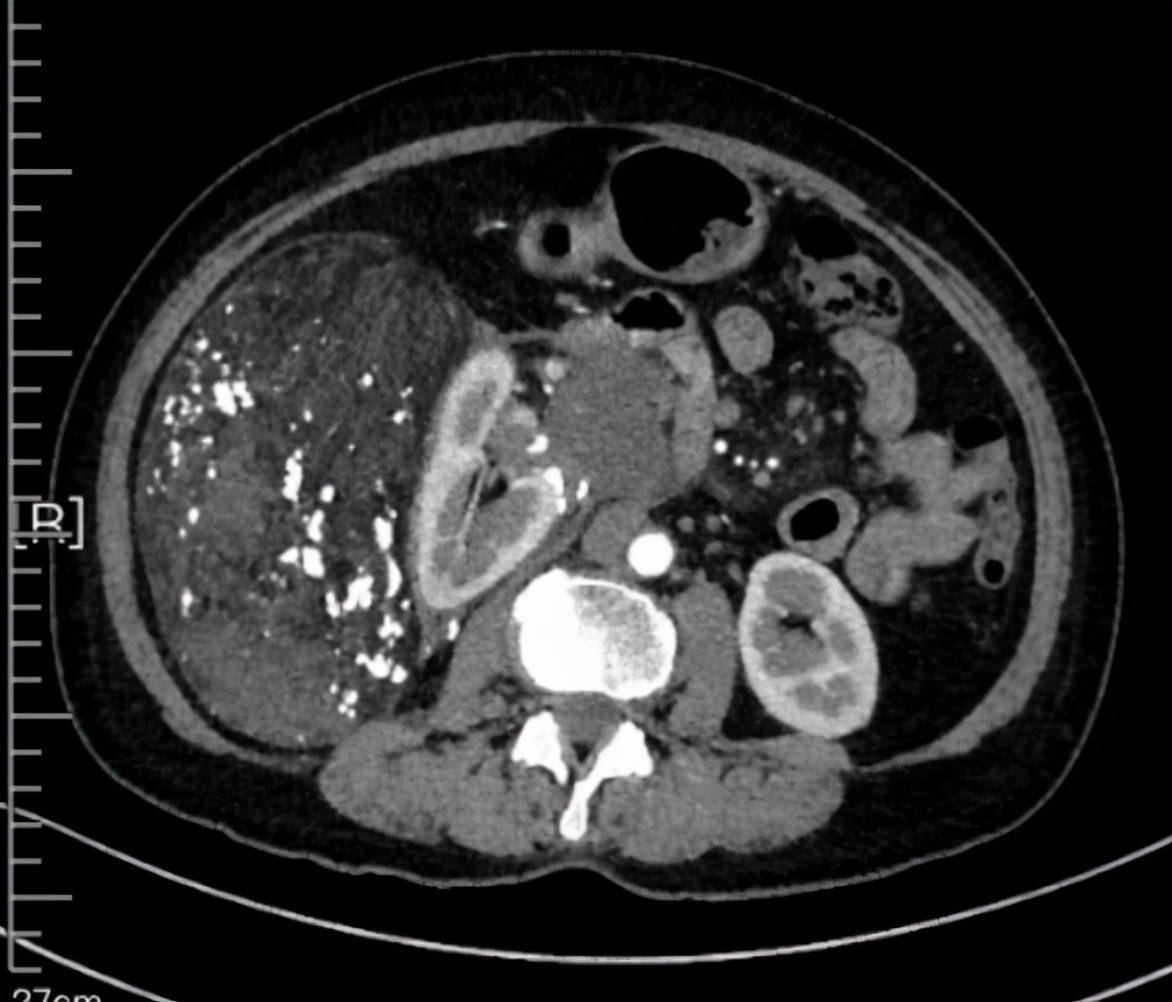

这个患者表现为右侧腹部后腹膜巨大肿瘤,上级侵犯到第二肝门,压迫下腔静脉和肝右静脉,右侧压迫下腔静脉,肿瘤侵犯下腔静脉上下,右侧侵犯肾门。肿瘤最右侧在腹主动脉左侧,直径超过25公分,压迫结肠十二指肠等。

术前